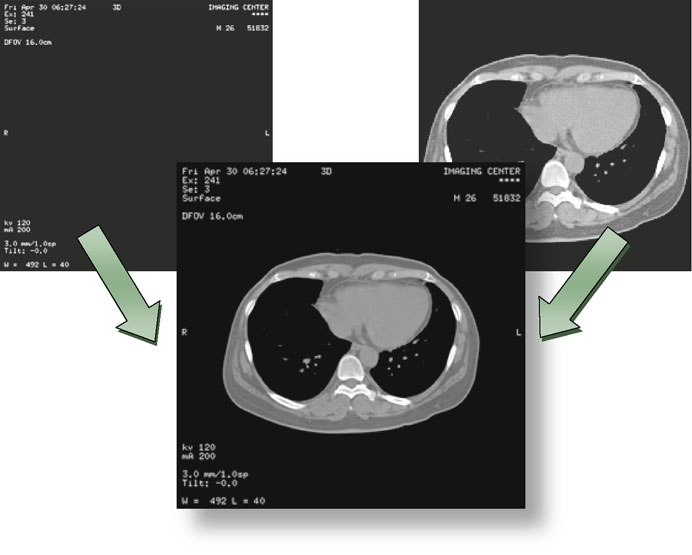

Hierarquia de Informação DICOM: Patient-Study-Series-Image

O DICOM organiza toda informação em quatro níveis hierárquicos que refletem o fluxo clínico real: Paciente → Estudo → Série → Imagem.

- Paciente: identificado pelo Patient ID

(0010,0020) - Estudo: identificado pelo Study Instance UID

(0020,000D) - Série: identificada pelo Series Instance UID

(0020,000E) - Imagem: identificada pelo SOP Instance UID

(0008,0018)

Essa hierarquia existe porque na prática clínica, um paciente pode ter múltiplos estudos (CT, RM, US), cada estudo contém séries com diferentes protocolos, e cada série possui uma ou mais imagens. UIDs garantem que cada entidade seja globalmente única — formato UI com até 64 caracteres compostos por dígitos e pontos, como 1.2.840.10008.1.2.